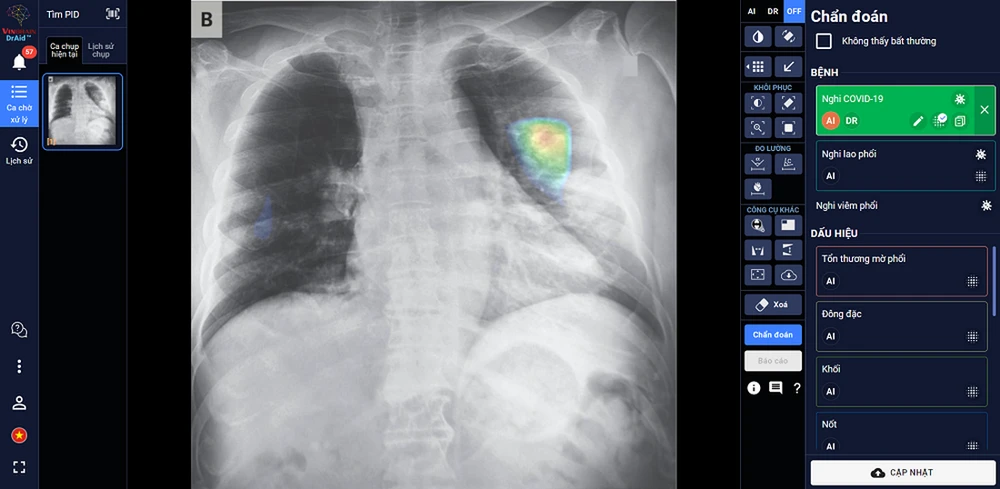

DrAid™ – phần mềm AI trợ lý bác sĩ đầu tiên tại Việt Nam - do các chuyên gia, nhà khoa học của VinBrain (công ty công nghệ thuộc Tập đoàn Vingroup) nghiên cứu phát triển thành công. DrAid hiện có khả năng hỗ trợ chẩn đoán 20 dấu hiệu bất thường và bệnh lý về tim - phổi - xương với độ chính xác trên 88% trong vòng 5 giây, đồng thời tự động đưa ra báo cáo y tế theo chuẩn quốc tế JCI có khoanh vùng và đo kích thước chính xác tại khu vực bất thường. Ngoài ra, tính năng “Hỏi ý kiến Bác sĩ thứ 2 (từ xa)” của DrAid™ hỗ trợ các bác sĩ gửi ảnh chụp trực tiếp từ máy chụp cho một bác sĩ khác để tham khảo ý kiến đối với những ca bệnh khó. Việc này giúp giữ nguyên chất lượng hình ảnh, đồng thời đơn giản hóa quy trình hội chẩn, giúp cho việc hội chẩn giữa hai bác sĩ diễn ra nhanh gọn, xóa bỏ các rào cản về địa lý và thời gian, đồng thời nâng cao chất lượng hội chẩn với gợi ý về chẩn đoán của AI.

Đặc biệt, DrAid™ mang lại 4 giá trị ưu việt trong phát hiện và điều trị COVID-19 dựa trên ảnh X- quang ngực thẳng gồm: Phát hiện nhanh góp phần sàng lọc mầm bệnh trong cộng đồng, song song cùng phương pháp xét nghiệm PCR. Kết hợp cùng xét nghiệm PCR từ đó nâng cao độ chính xác, giảm thiểu tình trạng âm tính giả tránh bỏ sót; Hỗ trợ đánh giá tiên lượng tình trạng bệnh nhân thông qua lịch sử hình ảnh chụp X-quang, để từ đó có hướng điều trị phù hợp; Hỗ trợ tăng tính nhất quán và chuyển giao kiến thức của bác sĩ từ tuyến Trung ương tới cơ sở.

DrAid™ chẩn đoán và tiên lượng điều trị bệnh nhân COVID-19 dựa trên hình ảnh X-quang ngực thẳng